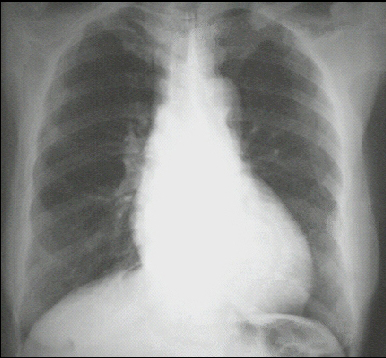

These chest X rays show left ventricular enlargement and a dilated aorta. The PA view demonstrates cardiomegaly, as evidenced by a cardiothoracic ratio greater than 50%. Note also the increased inferolateral cardiac border that is consistent with left ventricular enlargement due to volume overload. The ascending, transverse, and descending aortic shadows are also prominent.

The lateral view shows left ventricular enlargement, as evidenced by posterior displacement of the left ventricular shadow.